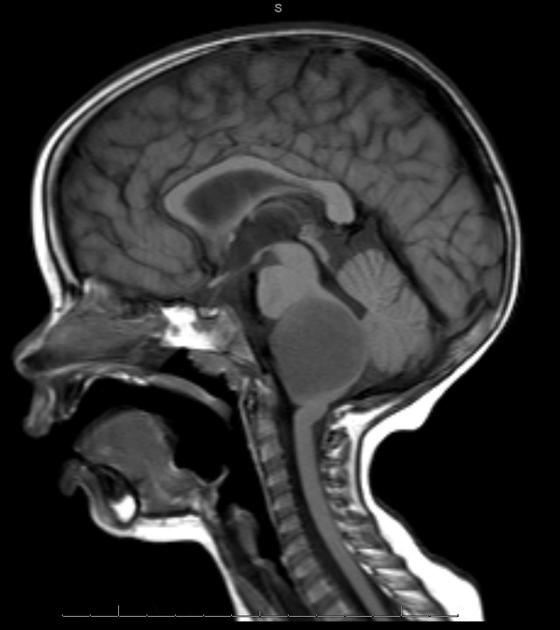

They appear on MRI T2 or FLAIR. The presence of ring enhancement suggests high grade disease. See Radiopedia for more images of diffuse pontine gliomas.

T1